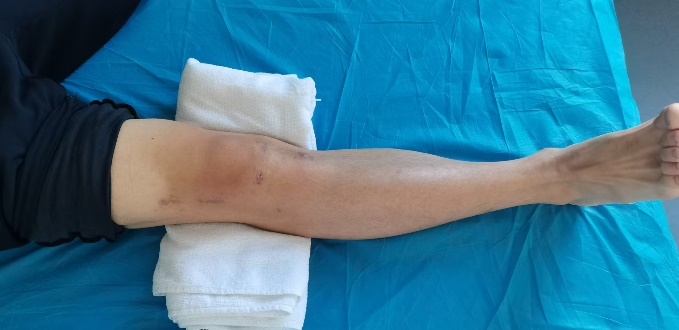

下肢骨折在日常生活中颇为常见,其成因繁杂多样,无论是意外事故,还是运动过程中的不慎损伤等,都有可能导致下肢骨折情况的发生。术后康复这一环节对于下肢功能能否顺利恢复以及生活质量能否有效提升,有着至关重要的影响,可谓举足轻重。本文将为您介绍下肢骨折术后康复的相关知识,帮助您更好地了解这一重要阶段,助力康复之路。

在下肢骨折术后,如果未能及时开展并坚持恰当的康复治疗,那么很可能引发一系列问题,例如关节变得僵硬、肌肉出现萎缩、下肢力量明显下降、平衡能力大幅减弱等,这些问题将会对行走、站立以及日常生活中的各种活动能力产生不利影响。与之相反,积极且有效的康复治疗不仅能够推动骨折的愈合进程,还能够增强肌肉力量、提升关节的灵活性,进而优化下肢的运动功能,降低并发症出现的几率,助力患者尽快回归正常生活。